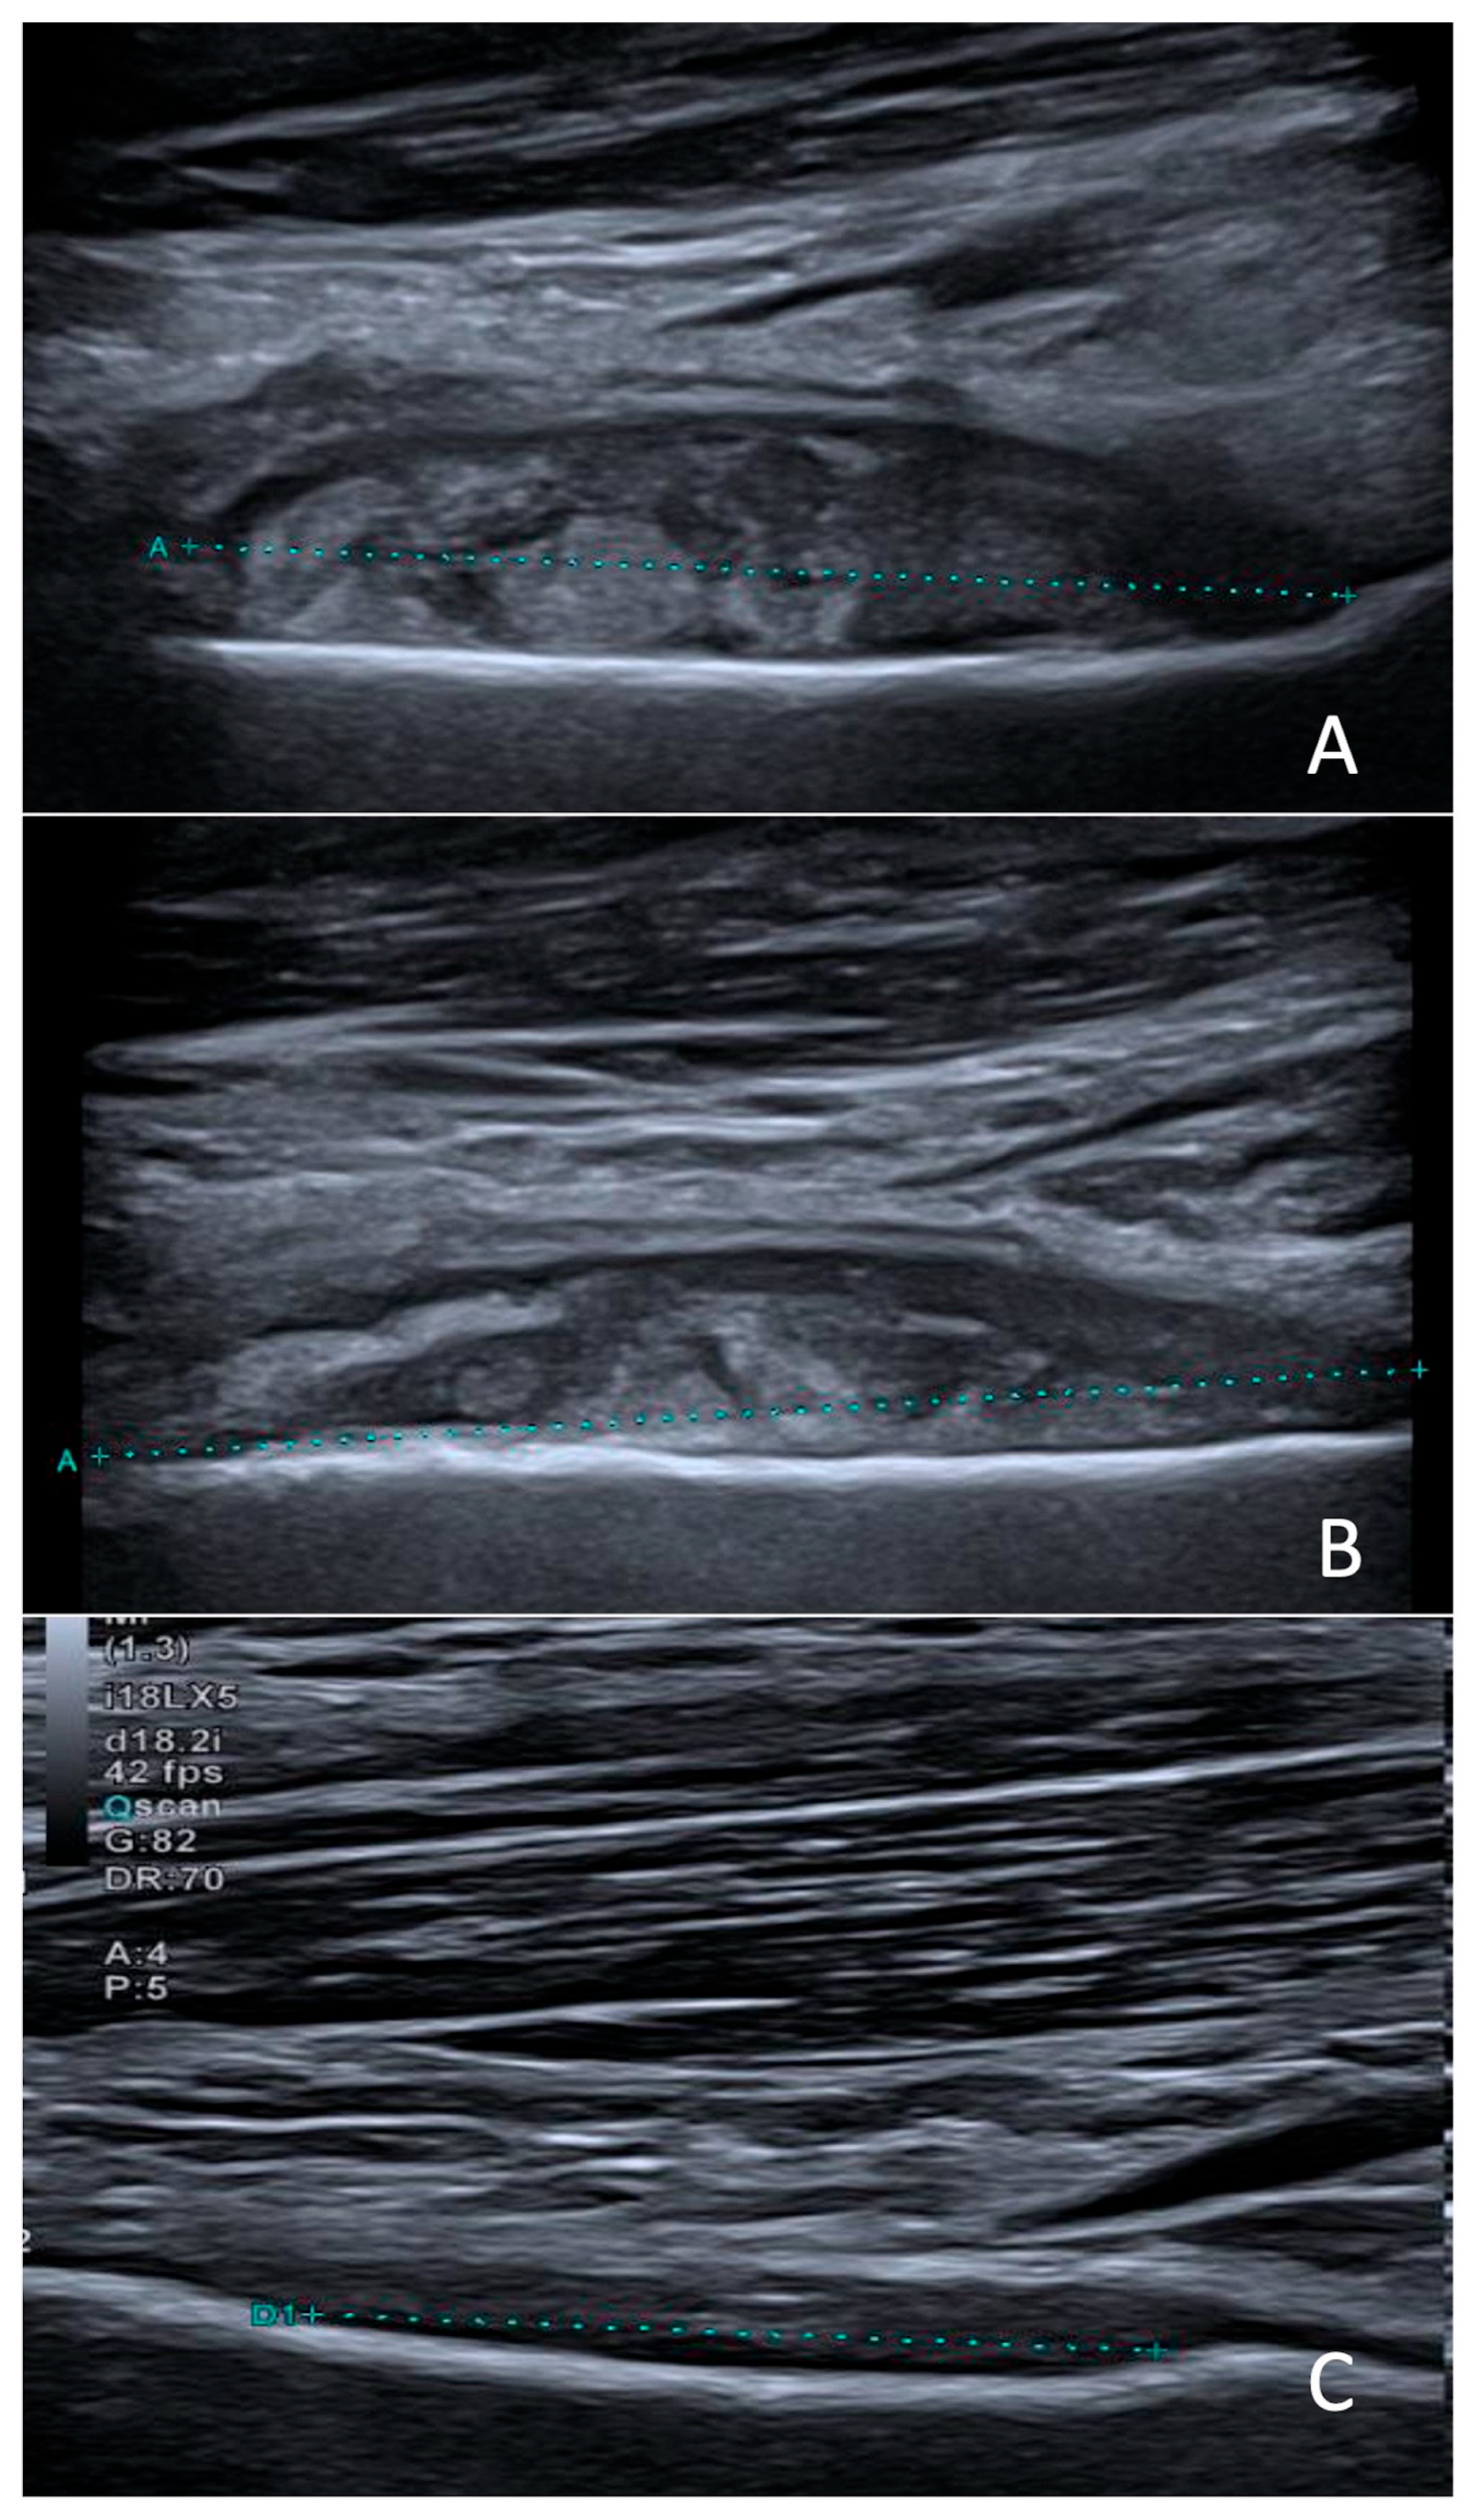

The collection could not be aspirated because of its deep location and anatomical inaccessibility. Clindamycin (40 mg/kg/day in 3 doses) was initiated for a total duration of 7 weeks. At one-month follow-up, the outcome was favorable, with complete resolution of the mobility restriction and control ultrasound showing a moderate decrease in the abscess size (Figure 2).

Figure 2. Sagittal ultrasound scans obtained at diagnosis (A), two weeks later (B), and three months after treatment initiation (C), showing progressive regression of the subperiosteal collection (between calipers).